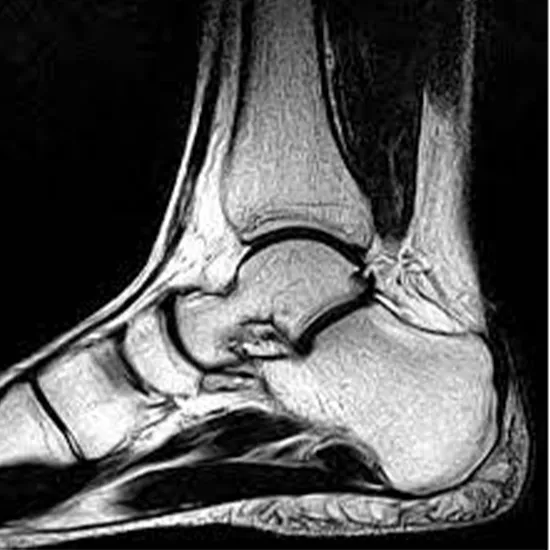

An ankle MRI is used to figure out what's causing pain, weakness, swelling, or bleeding in the ankle. It gives you detailed pictures of the bone, cartilage, muscle, and tendons inside your joint. Your doctor will tell you to get an MRI if you have severe ankle pain, a sports injury, less ankle movement, or problems with surgical devices that were put in.

MRI (Magnetic Resonance Imaging) screening of the Ankle Joint is a non-invasive radiology test used to evaluate the condition of the Ankle Joint and surrounding tissue. MRI Ankle Joint is done to look for Ankle Joint conditions and the surrounding area.